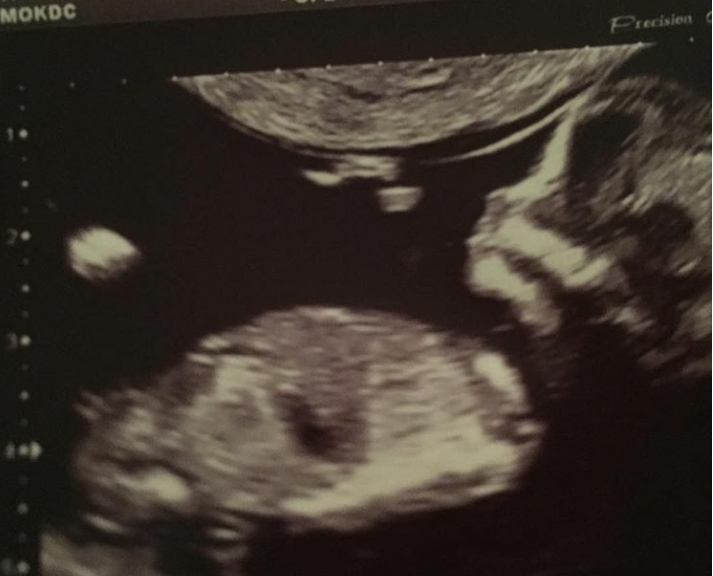

Помогите определить пол!

Больше на мальчика похож.

вроде мальчик)

Бугор на пацана похож

мне кажется, что девуля будет)) Напишите потом , кто оказался прав))

На таком сроке в любом случае попадание будет 50/50 и достоверно все равно никто не скажет..если только угадает не более, т.е. попадет в те самые 50%. Если сравнивать с фото узи Виктории, что ниже, то похоже на ваше фото узи, там только ножки чуть повыше вертикально, а на вашем горизонтально, но угол наклона бугорка одинаковый.